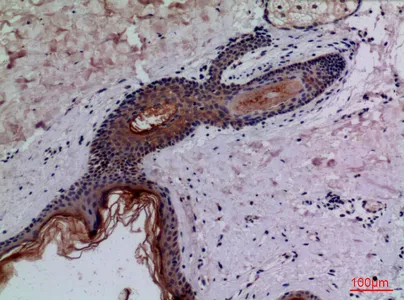

KiSS-1R Rabbit Polyclonal Antibody

Cat: APRab13039

Size1:50μl Price1:$118

Size2:100μl Price2:$220

Size3:500μl Price3:$980